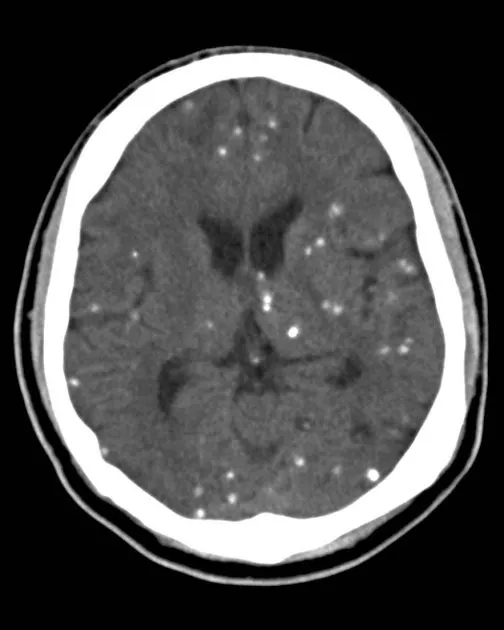

脑囊虫钙化

【病例讨论】颅内多发点状钙化灶 [病例帖]

脑囊虫病 特征性的散在的钙化结节,圆形或椭圆形,直径2

ct均表现为脑实质内多发散在结节样钙化;钙化均可位于双侧侧脑室周围

头颅ct(见下图):双侧小脑,基底节区,灰白质交界区广泛对称性钙化以及